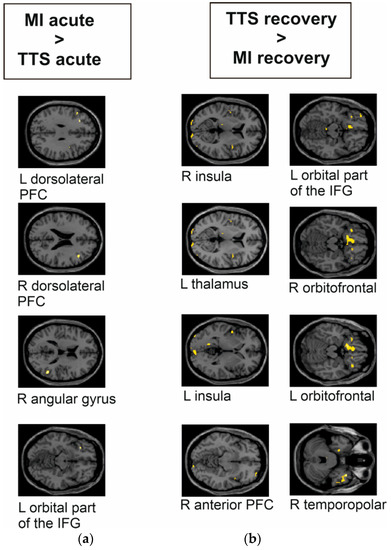

| Group Contrast | Number of Voxels | MNI Coordinate | Region | T Value | p Value |

|---|---|---|---|---|---|

| MI acute phase > TTS acute phase | 33 | 52, −52, 16 | R angular gyrus | 4.06 | 0.000 |

| 22 | 42, 24, 22 | R dorsolateral PFC | 3.97 | 0.000 | |

| 16 | −48, 22, 30 | L dorsolateral PFC | 3.82 | 0.000 | |

| 14 | −30, 28, −12 | L orbital part of the IFG | 4.13 | 0.000 | |

| TTS recovery phase > MI recovery phase | 168 | −12, 16, −18 | L orbitofrontal area | 5.06 | 0.000 |

| 86 | 40, 14, −30 | R temporopolar | 5.84 | 0.000 | |

| 51 | −32, 28, −14 | L orbital part of the IFG | 4.03 | 0.000 | |

| 30 | −46, 0, 0 | L insula | 4.07 | 0.000 | |

| 27 | 42, 0, 8 | R insula | 4.30 | 0.000 | |

| 13 | 32, 60, −10 | R anterior PFC | 4.13 | 0.000 | |

| 9 | 16, 28, −16 | R orbitofrontal area | 3.85 | 0.000 | |

| 6 | −14, −26, 8 | L thalamus | 3.76 | 0.000 |